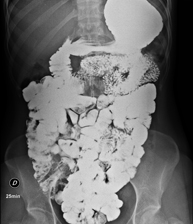

Tècnica que usa els raigs X a través de la qual s'obtenen imatges de l'abdomen (estómac, intestí prim, intestí gros, fetge, ronyons, bufeta, pelvis òssia, etc.) per al seu estudi. - RX Columna lumbar

Prova diagnòstica que consisteix en obtenir imatges radiològiques en moviment de l'esòfag, estómac, duodè i intestí prim mitjançant l'ús de raigs X (fluoroscòpia) i d'un contrast opac baritat que s'administra per via oral. - Ènema opac doble contrast

Prova diagnòstica que consisteix en obtenir imatges radiològiques de l'intestí gros (còlon i recte) mitjançant l'ús de raigs X. S'utilitza un contrast opac que s'administra a través del recte en forma d'ènema i també s'introdueix aire per expandir el còlon.

Una radiografia de tòrax és una tècnica mitjançant la qual, amb l'ús d'una petita dosi de radiació, s'obté una imatge bidimensional de la caixa toràcica i el seu contingut (pulmons, cor, mediastí, etc. ). És una de les proves mèdiques realitzades més comuna. - RX Abdomen

Una radiografia d'abdomen és una tècnica mitjançant la qual, amb l'ús d'una petita dosi de radiació, s'obté una imatge bidimensional de l'abdomen amb les seves estructures anatòmiques (estómac, intestí prim, intestí gros, fetge, pàncrees, ronyons, bufeta, pelvis òssia, etc.) - Telerradiologia columna